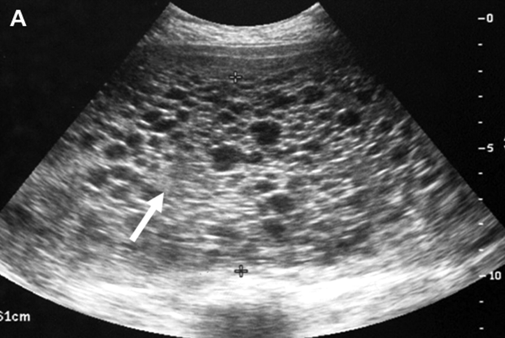

Appears as snowstorm on USS, with hydropic villi + large theca lutein cysts

USS - snowstorm appearance, large lutein cysts